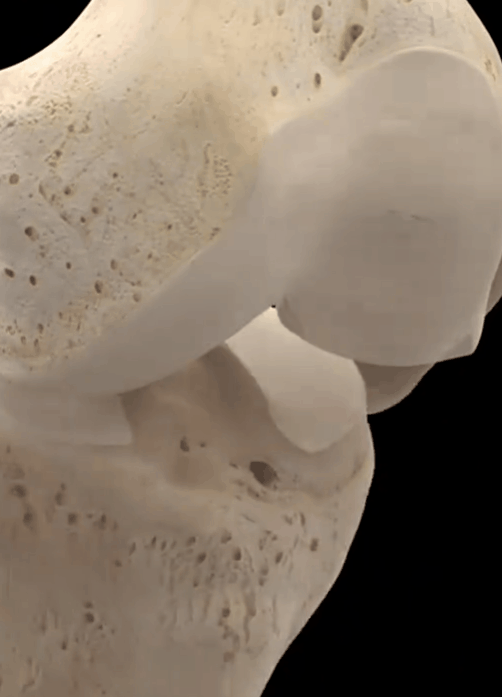

Comme vous pouvez le voir sur la photo ci-dessous, les articulations se sont typiquement développéesLacunes visibles, formation osseuse réduite, ostéoporose des articulations plus lourdesSi un tel patient présente des sensations et des douleurs anormales évidentes, l'injection intra-articulaire de vitrate de sodium ou l'administration constante d'analgésiques par voie orale le feront souffrir énormément, ce qui ne l'aidera pas vraiment à résoudre le problème.

Sur la surface des os de l'articulation du genou, il y a une couche de cartilage attachée, généralement dans l'articulation du genou sous une charge de pression excessive, ce sera à cause de l'usure du cartilage, dans nos activités, montrant la douleur ; l'usure du cartilage progressivement aggravée, conduira à l'os de la cuisse et l'os du mollet collision dure, la perte de la stabilité de l'articulation, et progressivement il y a ostéomalacie, la détérioration de la circulation sanguine, le refroidissement et le bruit d'éclatement est inévitable.

Dans les articulations du genou, la surface articulaire est recouverte d'un cartilage fin et lisse afin de permettre un mouvement suffisamment souple, et en cas d'usure due à une blessure ou à une surutilisation, la surface articulaire devient inégale, et l'os glisse sur la surface inégale pendant le mouvement de l'articulation, ce qui entraîne un bruit de cliquetis. Lorsque l'articulation bouge, l'os glisse sur la surface inégale de l'articulation et un bruit de cliquetis se produit, qui peut s'accompagner d'une douleur intense.

- fricatif--Lorsque le cartilage articulaire est très usé, les extrémités des os sous-chondraux perdent la protection du cartilage et le frottement direct émet un bruit de frottement faible et rauque ; les débris de cartilage qui se promènent dans la cavité articulaire provoquent aussi facilement des blocages, ce qui donne lieu à un bruit de frottement articulaire. Les patients doivent faire la distinction avec le claquement physiologique normal, les critères de jugement sont très simples, le claquement pathologique est souvent accompagné de symptômes d'inconfort articulaire.